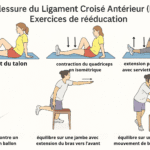

Lésions méniscales ou ligamentaires non traitées

Une lésion du ménisque, même ancienne, peut se réveiller en position allongée. Le genou devient douloureux lors d’un mouvement involontaire la nuit. Les douleurs ligamentaires post-traumatiques sont aussi fréquentes après une entorse mal soignée.

Des exercices de mobilité articulaire douce avant le coucher améliorent la circulation locale et réduisent la douleur. Étirez les ischio-jambiers et les quadriceps pendant 5 à 10 minutes.